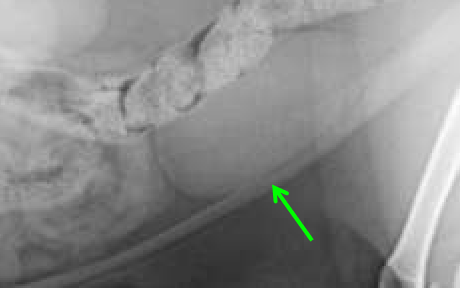

Serosal Detail

contrast between abdominal organs and the ability to see their edges

Border effacement

2 structures of the same opacity are in contact, so their margins cannot be distinguished